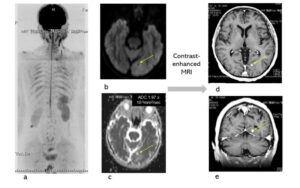

Fig. Case 4. Squamous cell carcinoma. pT3N0M0. Whole body imaging in DWIBS (a). Tiny brain metastasis was presented in DWIBS (b). The ADC of the brain metastasis in ADC map was 1.94x 10-3mm2/sec, and it was a false negative (c). Enhanced brain MRI was added to conform the brain metastasis. DWIBS could be useful to detect a brain metastasis. The DWIBS-enhanced lesion (ADC 2.04 x 10-3mm2/sec) at the level of rt. kidney, which was located in abdominal wall and had not changed for one year, was diagnosed a benign neurogenic tumor.